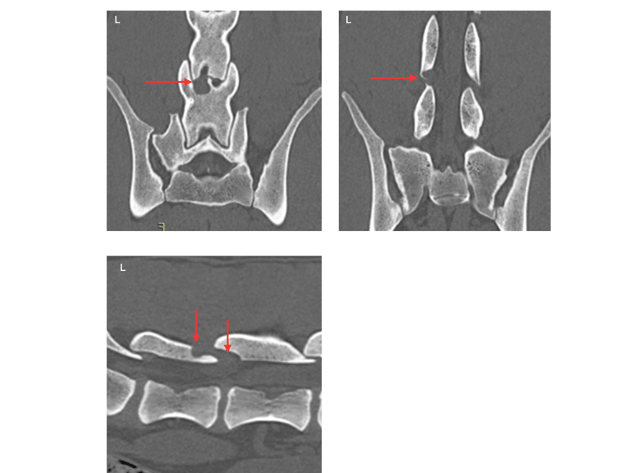

Het CT-onderzoek toont een extramedullaire weke delentoename links in het wervelkanaal. Deze structuur breidt zich uit in het foramen intervertebrale en naar dorsaal ter hoogte van het facetgewricht. In het wervelkanaal is lokaal matige compressie op het ruggenmerg. Er is een vrij regelmatig begrensde (‘geografische’) osteolyse van de lamina en het processus articularis van L6 en L7 zichtbaar dorsaal van de weke delenstructuur. Het foramen toont verbreed. Er is geen duidelijke contrastopname van de weke delenstructuur zichtbaar. Verder is rechts ventraal spondylose aanwezig en geringe sclerose van het wervellichaam. Ook op de LS-overgang is matige ventrale spondylose zichtbaar en tonen de foramina gering benig vernauwd.

Het CT-onderzoek in botsetting toont de osteolyse en het verbrede foramen links.

Het CT-onderzoek in weke delensetting toont de weke delenmassa links en dorsaal in het wervelkanaal (gele pijl). De rode pijl toont het ruggenmerg